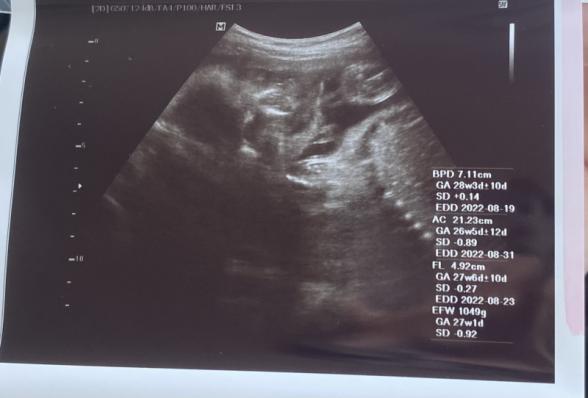

現在34週の妊婦です。今までもらったエコー写真を

整理して見返してたら胎児の鼻がちゃんと写ってなくて

鼻の骨がなかったり鼻が低いと生まれた時に異常があって産まれてくると聞いて心配になりました。

この写真から鼻に関して異常とか分かりますか?

赤ちゃんのお鼻がちゃんと写っていないということなのですが、お鼻の骨かなと思われるものは写っているように思いました。

異常になるのかどうかはわかりませんが、ちゃんとお鼻の骨はあるように思いました。

またかかりつけの先生にもご確認いただけたらと思います。